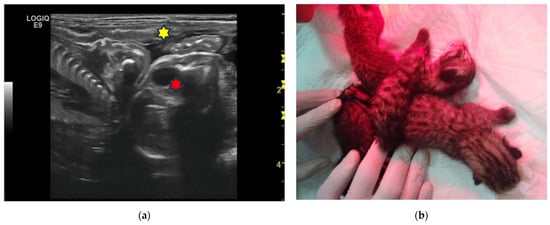

| 7C | 3-year-old Golden Retriever female dog | 50 | 14 | Monochorionic twins, morphologically comparable to the other foetuses. | C-section. Twins alive and of opposite sex, slightly dysmature. |